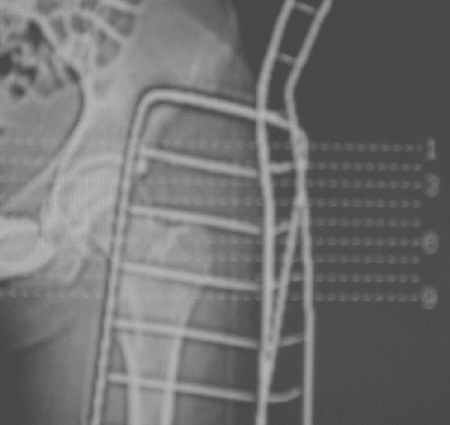

После рентген дообследования складывается мнение об отрыве дистального конца связки головки бедра с костным фрагментом головки (КТ2 скан 3, 4, КТ3 скан 1, прямая проекция - нижнийот 19.05). Данный вариант травмы встречается не часто, но известен, если мне не изменяет память, например см. Мюллер М.Е., Алльговер М., Шнайдер Р., Виллинеггер Х. Руководство по внутреннему остеосинтезу. - Springer-Verlag, 1996. - 750 с. С моей точки зрения, оптимально было бы остеосинтез головки, в обязательном порядке с сохранением целостности связки головки бедра. Как это технически выполнить - вопрос не простой. Кто знает и делал ???

Уважаемые коллеги! Заканчивая обследование больного с переломо-вывихом бедра сделал ему обычные R-томограммы. Кажется удалось "поймать" и отломок и донорское место. Мои выводы - в скиаграмме. Считаю, что это передне-нижний фрагмент головки, образовавшийся вследствии отрывного перелома. На томограммах отломок обозначаю длинной стрелкой, а место откуда он оторвался - более короткой. Учитывая тот факт, что его размеры по КТ 25 х 15 мм считаю, что его фиксация на место необходима для профилактики артроза, что при 16-ти летнем возрасте пациента важно в плане максимального отодвигания эндопротезирования. Планирую оперировать его 24.05.05 г. Результаты представлю.

Несколько соображений к "картинкам". На прямом снимке и КТ-томограммах все типичные линии вертлужной впадины: крыша, передняя стенка, задняя стенка - сохранены. На КТ-сканах 6 и 7 появляется фрагментация головки. С учетом R-томограмм отломок расположен спереди-снизу, а не сзади-сверху от сустава, как написано в описании КТ.